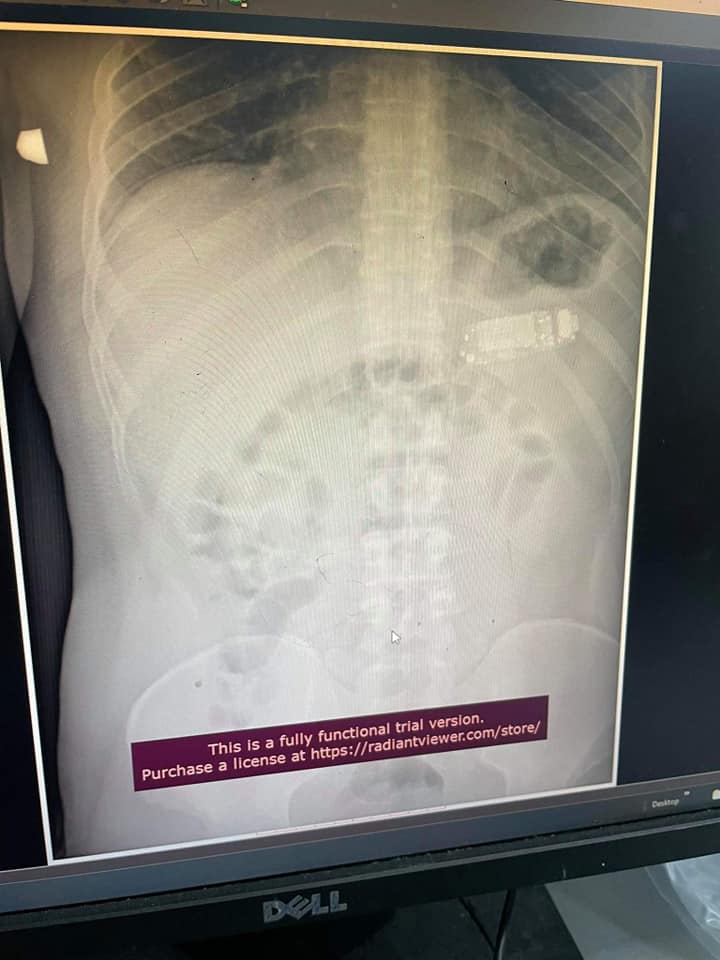

Мужчине сделали рентген и на снимке действительно обнаружили мобильный телефон с кнопками.

Хирургам пришлось провести сложную операцию и разделить телефон на три части с помощью эндоскопии. Посторонний предмет был слишком большим, чтобы желудок мог его переварить. Тем более, пациент был в опасности – аккумуляторная кислота могла вытечь и спровоцировать сильное отравление.

Стоит отметить, что хирурги справились с операцией без разрезания желудка. Все части телефона достали с помощью эндоскопа. Операция прошла успешно, без осложнений и пациент чувствует себя хорошо.